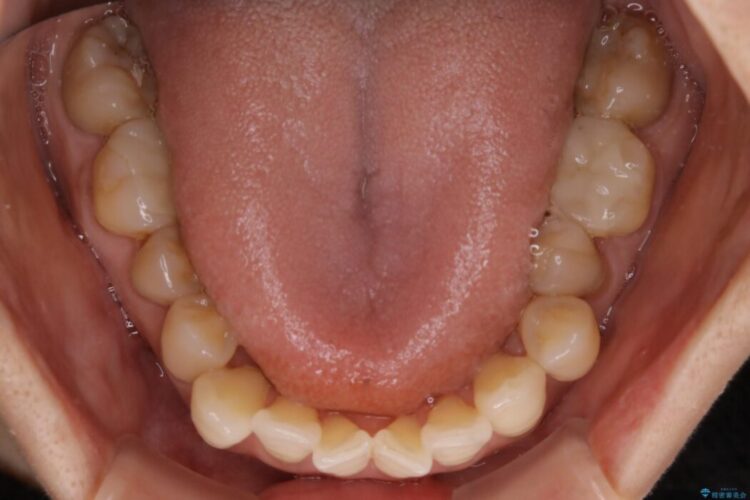

全体的に歯列が狭窄しており、本来外側に覆いかぶさっている上の前歯が内側に入り込んでいました。

歯並びが悪くなる原因の一つに「歯列弓の狭窄」というものがあります。

奥歯や前歯が内側(舌側)に倒れ込んでしまったり、歯が生えてくる位置が内側になってしまうことにより歯並びのアーチが狭くなってしまうことを言います。

このような場合、歯並びのアーチを拡大してあげるだけでもガタつきを無くすためのスペースがかなり作れることがあります。